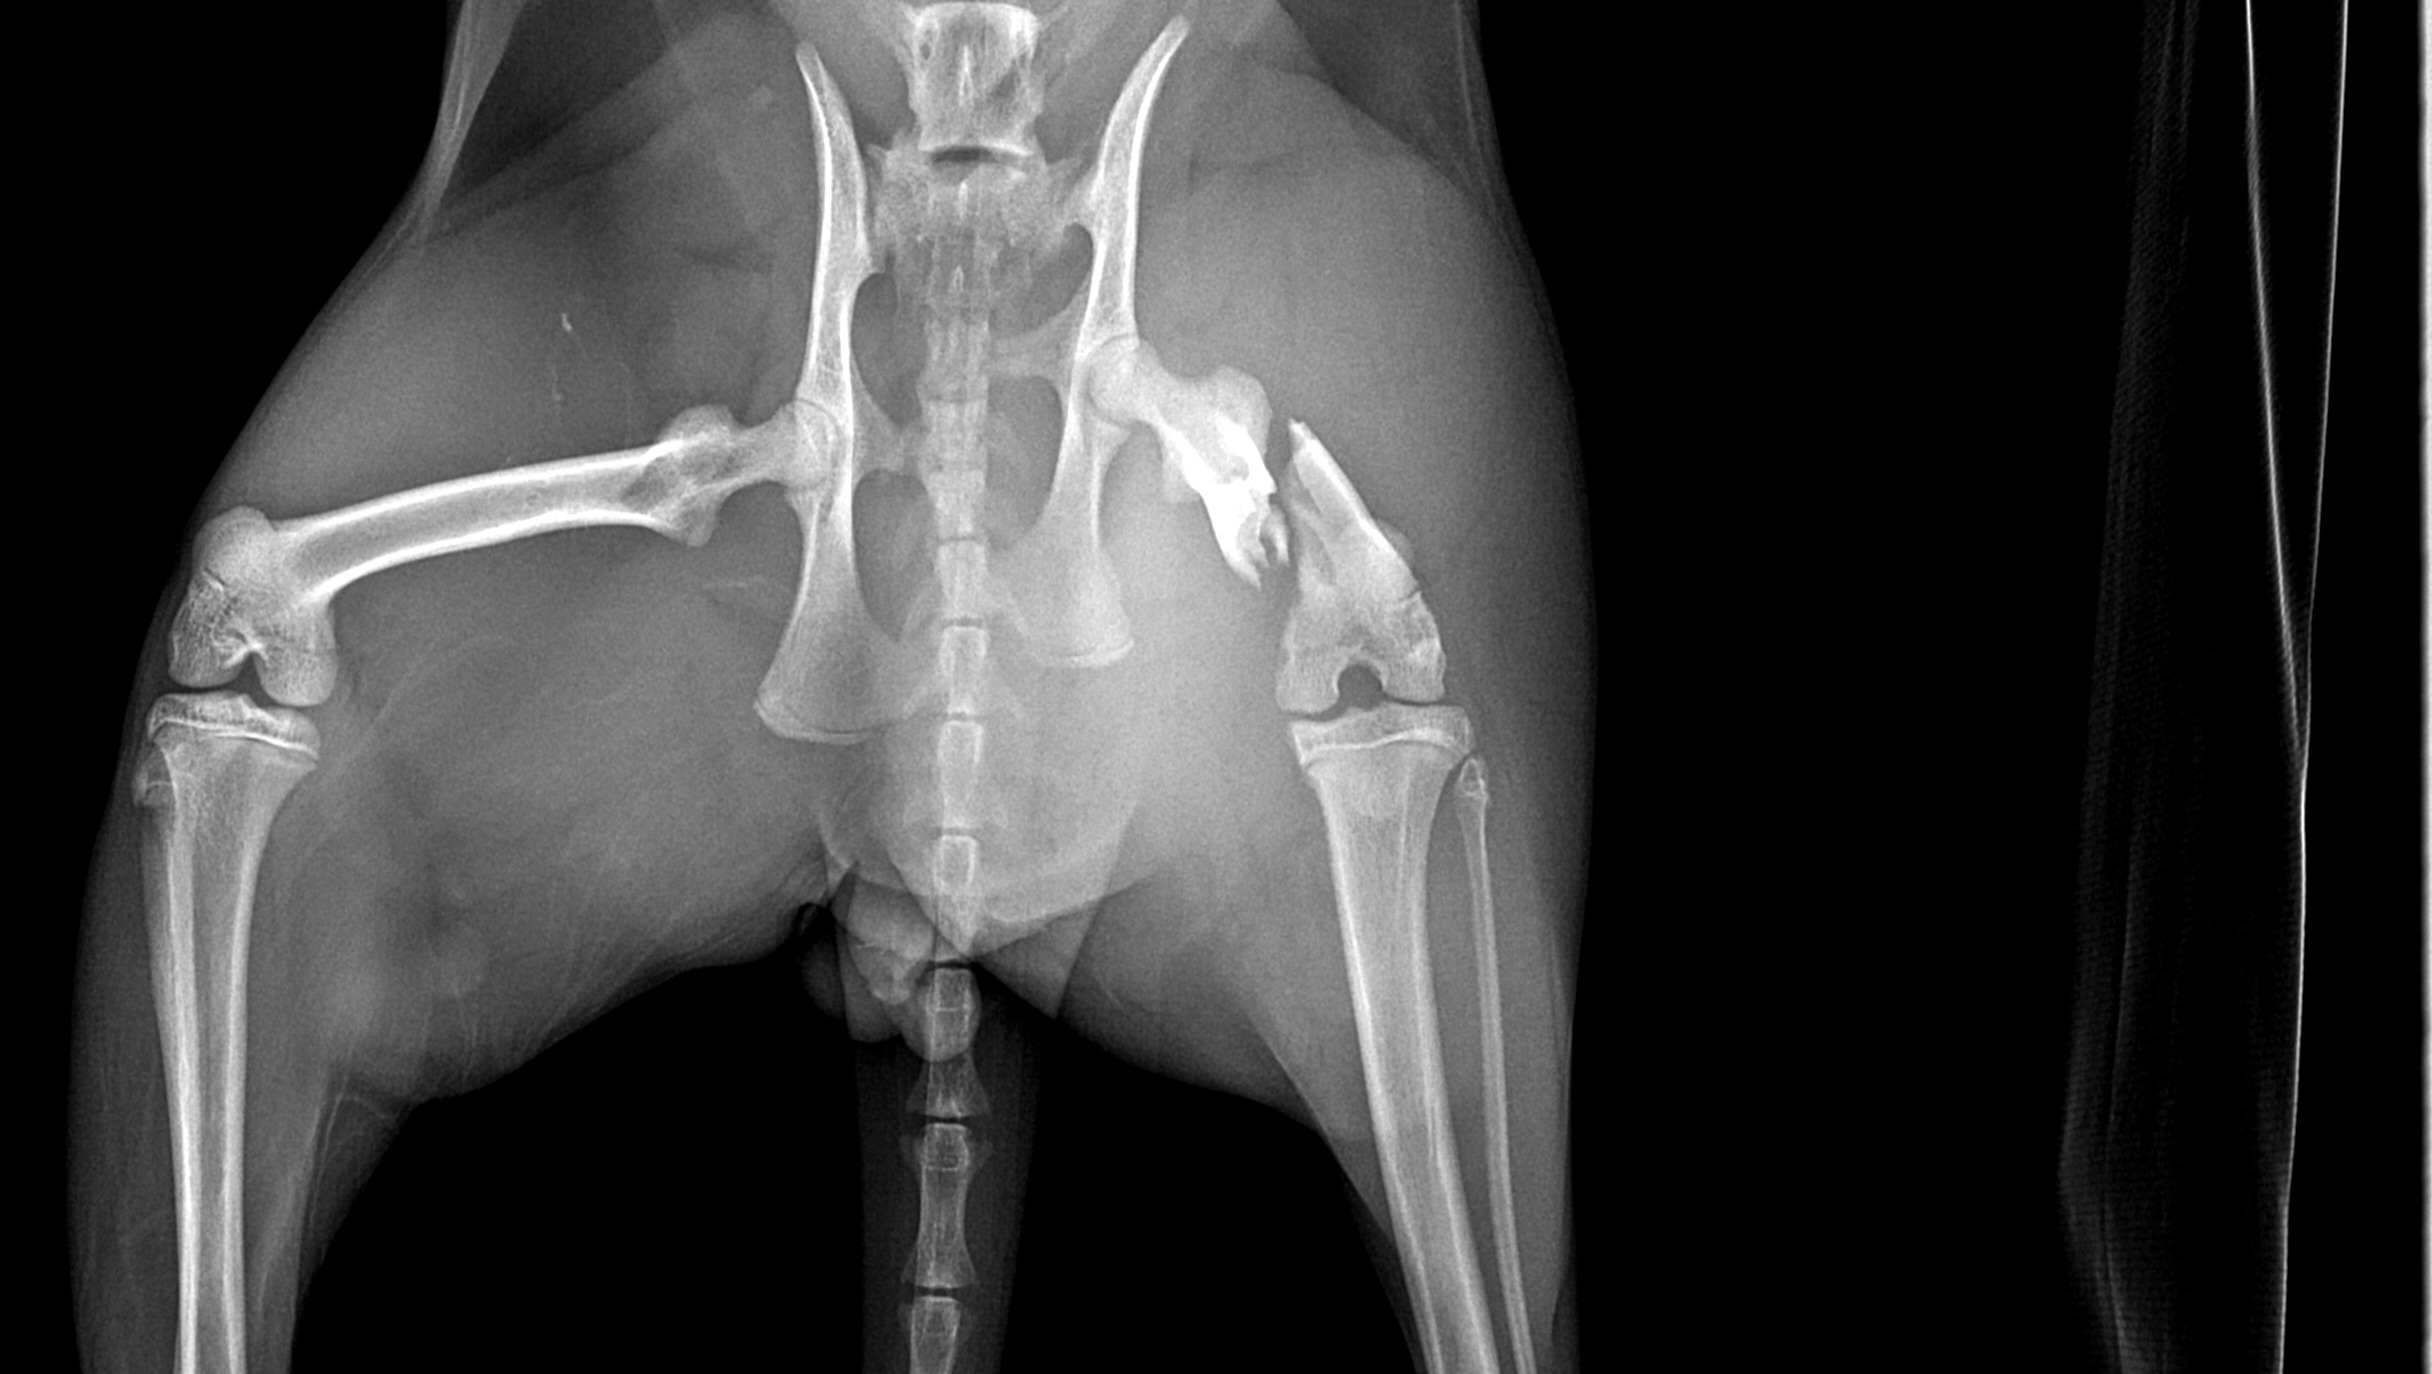

Our sweet angel of a kitten is seriously injured. His name is Nugget, he is an orange tabby and he is 7 months old. We found out that his pelvis was snapped in half, and his femur was shattered. He was likely hit by a car or was trapped by an animal that pulled his leg. He is going to need surgery to walk again, but we can't afford to save him. We want to help him as much as we can, but are struggling to support his healing journey. Please help bring our baby home safely!

His checkups, bloodwork, x-rays, and prognosis have come out to a total of 1,620, and his surgery was quoted for 3,800.